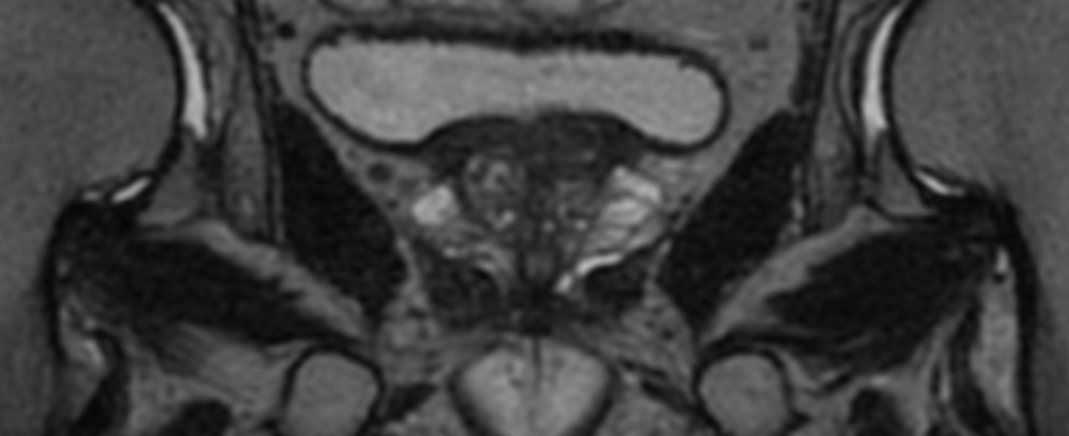

Coronal T2w TSE FatSat